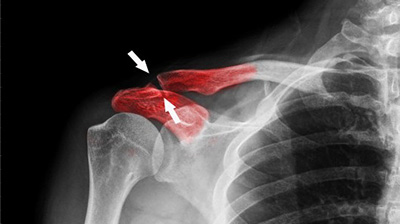

Когда кость ужасно деформирована в результате перелома или установленный несколько лет назад протез начинает давать вызываемые использованными при его изготовлении материалами побочные эффекты, костный трансплантат часто требуется, чтобы гарантировать возможность восстановления...